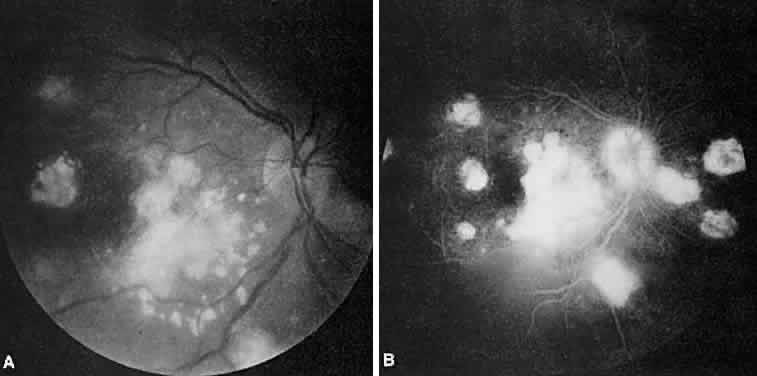

SARCOIDOSIS

Sarcoidosis is a systemic, idiopathic, noncaseating, granulomatous disease that affects various organs, including the eye, brain, lung, and skin. Ocular findings may include conjunctival nodules; anterior iridocyclitis; vitreous cells; retinal, optic nerve, and choroidal granulomas (Fig. 7A); retinal vasculitis (venules are preferentially affected); cystoid macular edema; retinal vessel occlusion; and disc and retinal neovascularization.

Fig. 7. Sarcoidosis. A. Choroidal granuloma. B. Fluorescein angiogram shows staining of the choroidal granuloma.

The FA reflects the various clinical entities. Retinal venular walls stain, particularly where there are perivenular exudates.25–27 More extensive venous involvement can produce a picture of dilated veins and perivenous leakage.27 Peripheral neovascularization occurs near areas of retinal capillary nonperfusion.25,28 Optic disc granulomas and optic disc neovascularization both leak extensively (Fig. 8A); sarcoid retinal lesions also stain (see Fig. 7B).27 In disc edema, the disc is hyperfluorescent and leaks fluorescein (see Fig. 8B).25

Fig. 8. Sarcoidosis. A. Fluorescein angiography shows two separate areas of neovascularization of the peripheral retina. B. Extreme leakage of dye from the right disc with cystoid macular edema of the right macular region in a patient with chronic sarcoidosis.

Four main patterns can be identified with ICG angiography. The first and most common pattern is hypofluorescent dark spots in the early and intermediate phases of the angiogram. These spots either become isofluorescent or remain hypofluorescent in the late phases. The second pattern is focal hyperfluorescent spots seen in the intermediate and late phases. The third pattern is fuzzy choroidal vessels due to perivascular choroidal leakage in the intermediate phase. Finally, the fourth pattern is characterized by diffuse zonal hyperfluorescence representing choroidal staining in the late phase of the angiogram. The latter two patterns resolved after systemic corticosteroid treatment.29